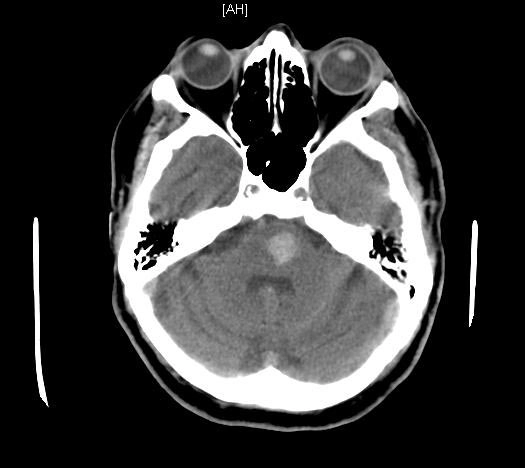

• Xuất huyết não do tăng huyết áp (Hypertensive Intracerebral Hemorrhage - HICH)